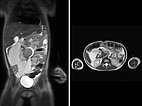

The first case is a 5-year-old girl with distended abdomen. On coronal and transverse T2-weighted, fat-suppressed MRI, an extensive macrocystic lymphatic malformation is visible with large cysts displacing the bowel.

Fat-saturated, T2-weighted MRI in three planes reveals the cause: retroperitoneally located giant cysts due to a macrocystic lymphatic malformation.